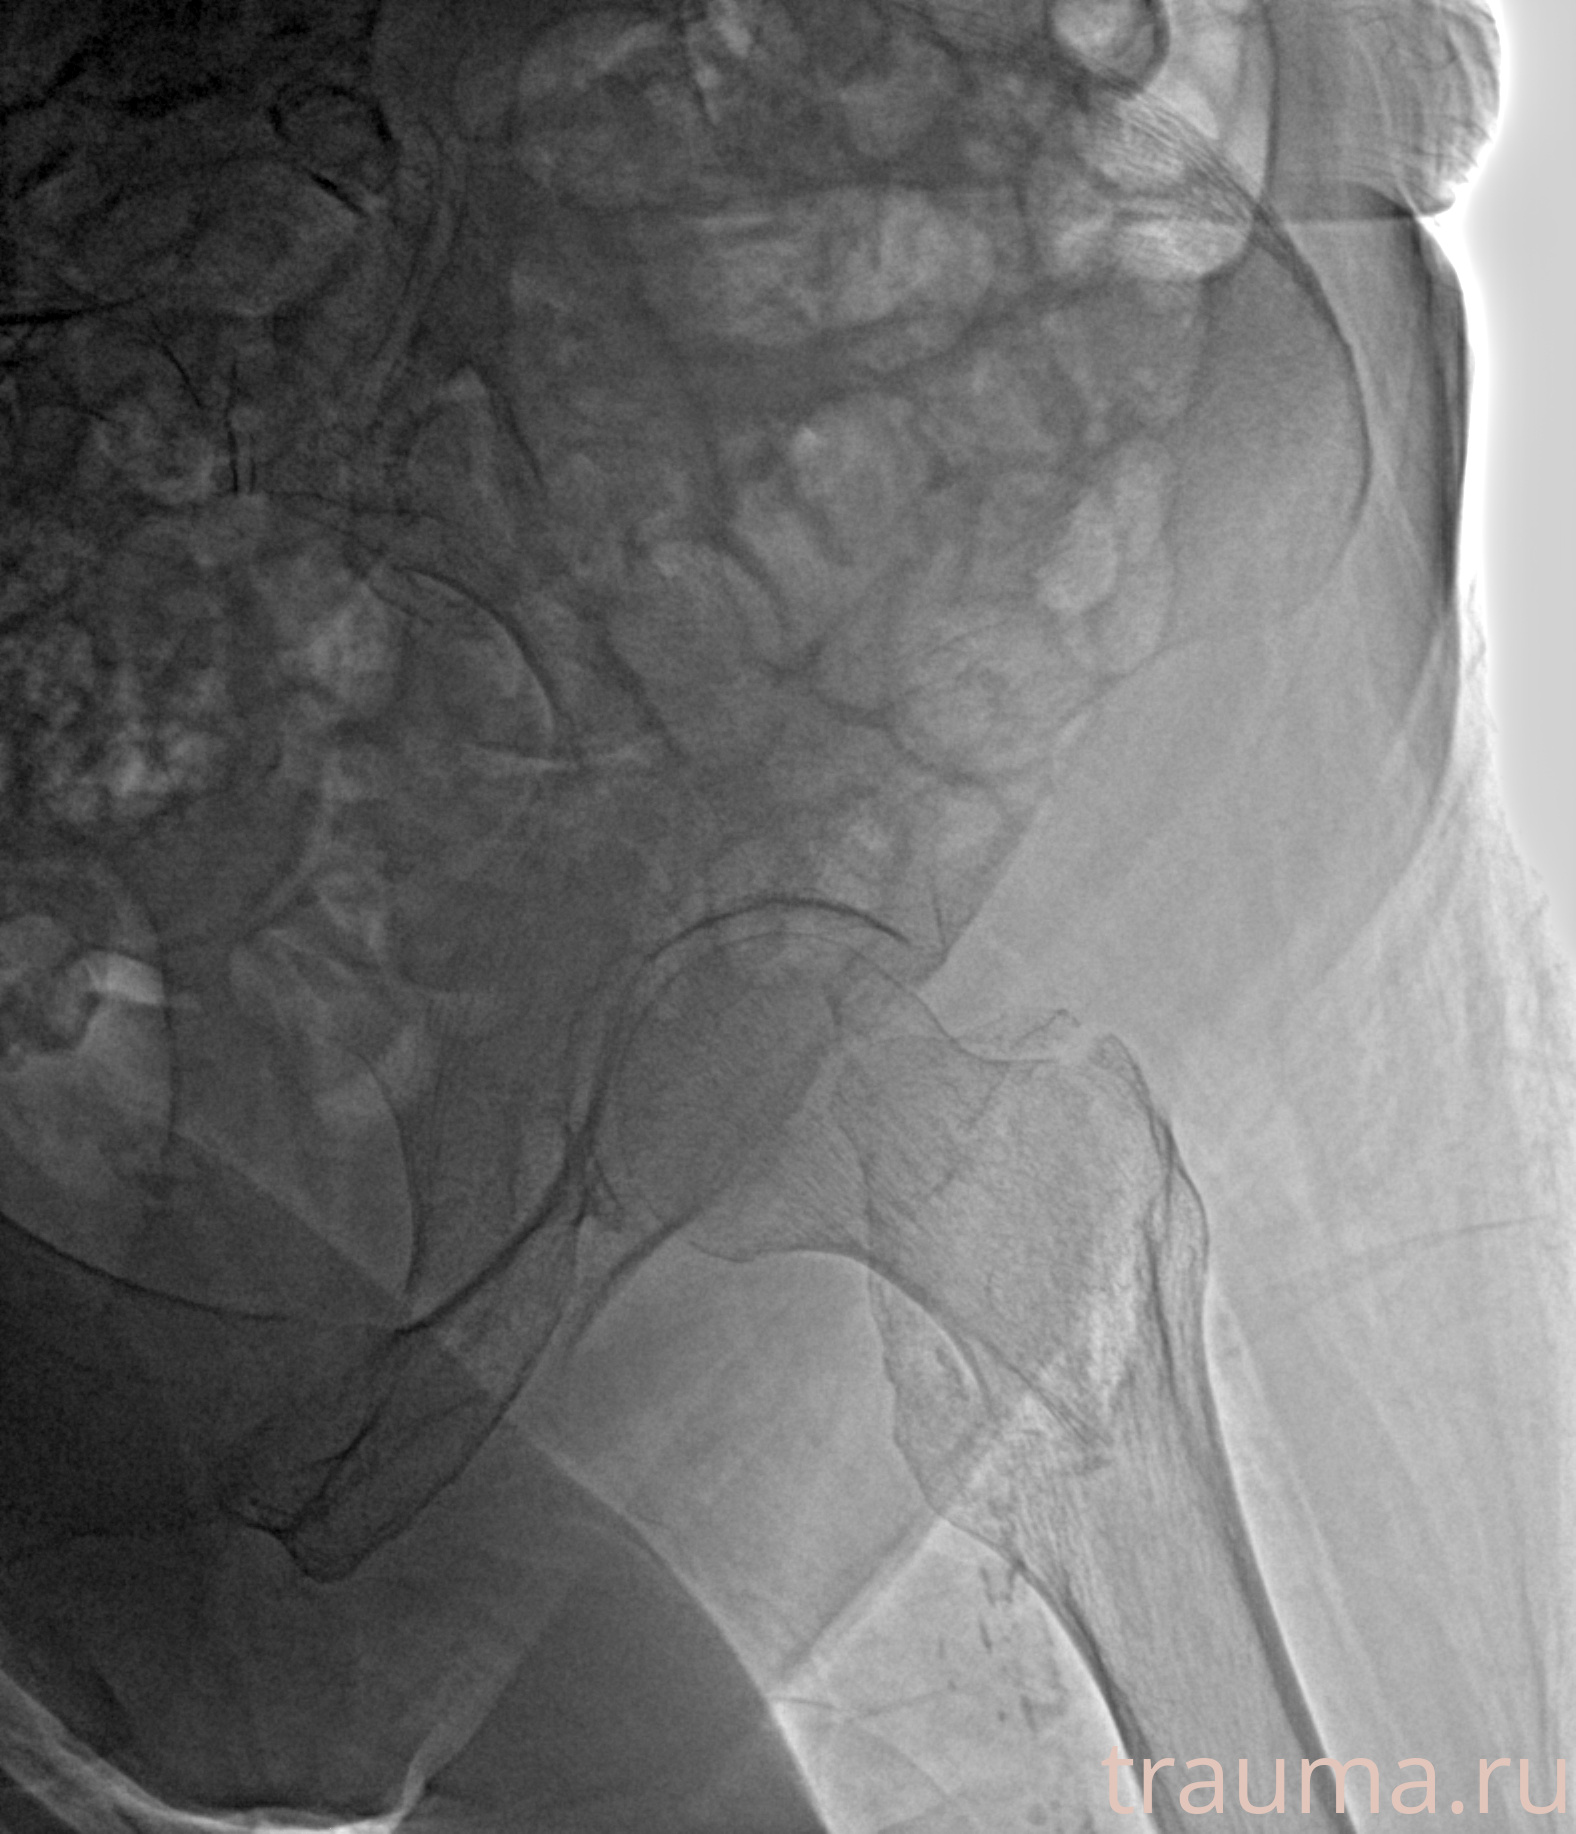

Рентгенограммы

Рентген на дому: по вашему адресу приезжает врач-рентгенолог, травматолог-ортопед с мобильным рентгеновским аппаратом, проводит диагностику травмы или заболевания, делает необходимые рентгенограммы, дает рекомендации по дальнейшему лечению. Получить качественные снимки в домашних условиях возможно благодаря уникальной методике, разработанной МосРентген Центром для института  Склифосовского